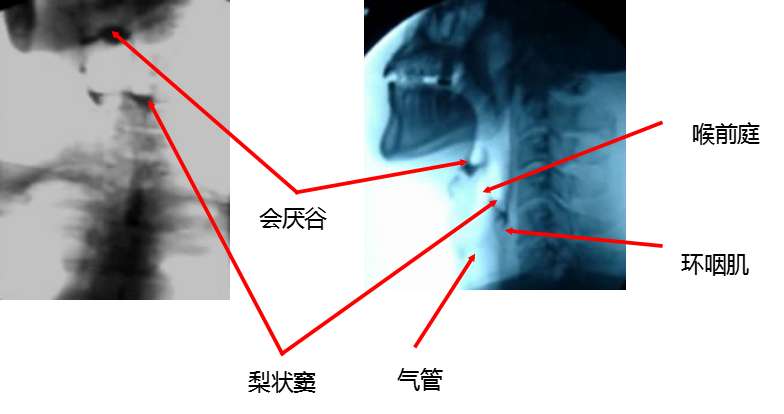

在此情况下,我院为患者进行了吞咽功能障碍X线钡餐造影检查。这项技术通过特殊的造影剂,清晰展示出患者的整个吞咽过程,从而精准识别出吞咽障碍的具体表现和原因。这不仅有助于我们了解患者的病情,更为后续的临床治疗方案提供了科学、准确的依据。

独特优势:自口咽至食管上段的过程十分迅速,只有X线动态造影录像或快速摄片才能记录其活动,并且可以逐步慢速回放。此外,吞咽造影检查还可以用于协助诊治吞咽障碍,被视为吞咽障碍的“理想”方法和诊断的“金标准”。通过食团的传送,在正位、侧位动态观察咽部运动,为治疗吞咽功能障碍提供了有效依据。